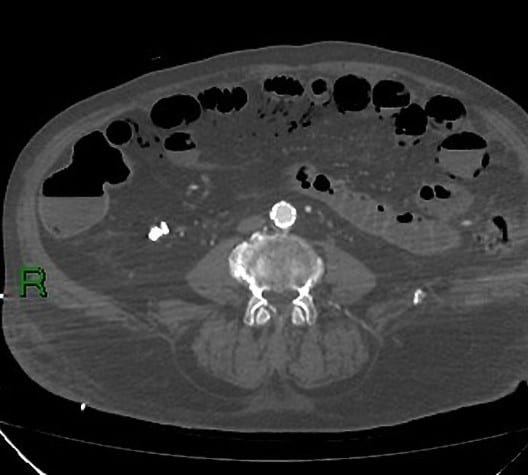

Nhồi máu ruột

» Thông tin: Nam giới – 85 tuổi.

» Lâm sàng: Đau bụng cấp.

# Dày thành ruột – Khí thành ruột – Khí tĩnh mạch mạc treo.